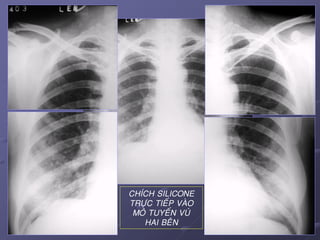

CHÍCH SILICONE

TRÖÏC TIEÁP VAØO

MOÂ TUYEÁN VUÙ

HAI BEÂN

42April 25, 2017